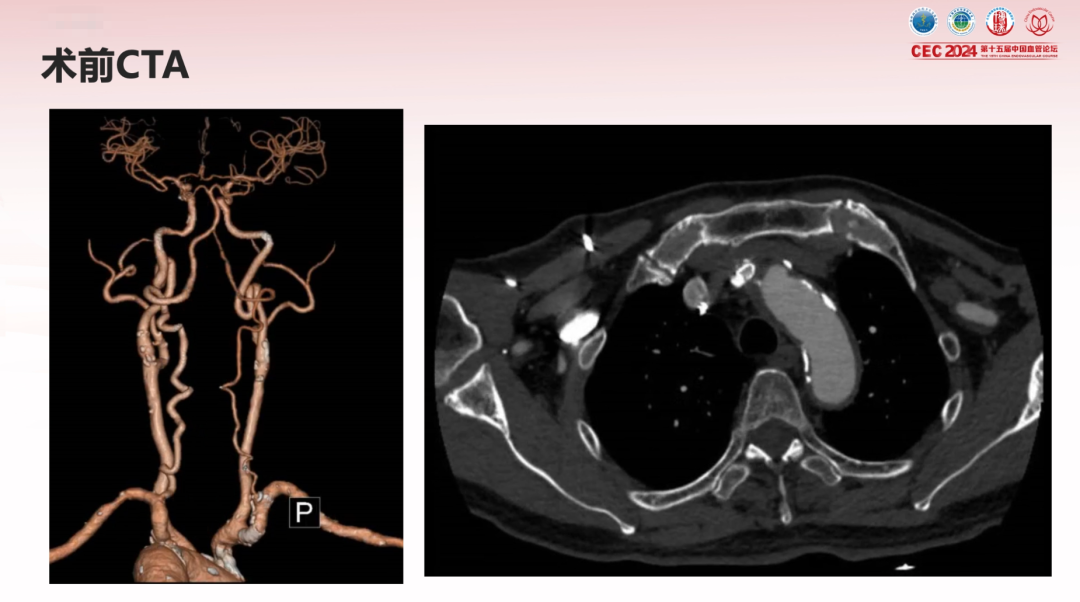

术前超声:右锁骨下动脉支架内血流通畅;无名动脉支架内狭窄,最窄内径0.18cm,流速达668cm/s,外径0.65cm,直径狭窄率70%-80%。

CTA:主动脉及头壁动脉多发斑块,无名动脉起始部支架内重度狭窄。

主动脉弓上造影显示无名动脉起始支架内重度狭窄,右椎动脉显影延迟,解除无名动脉支架内狭窄,恢复血流通畅,同时保障脑保护,降低并发症风险。

无名动脉起始支架内重度狭窄右椎动脉显影延迟